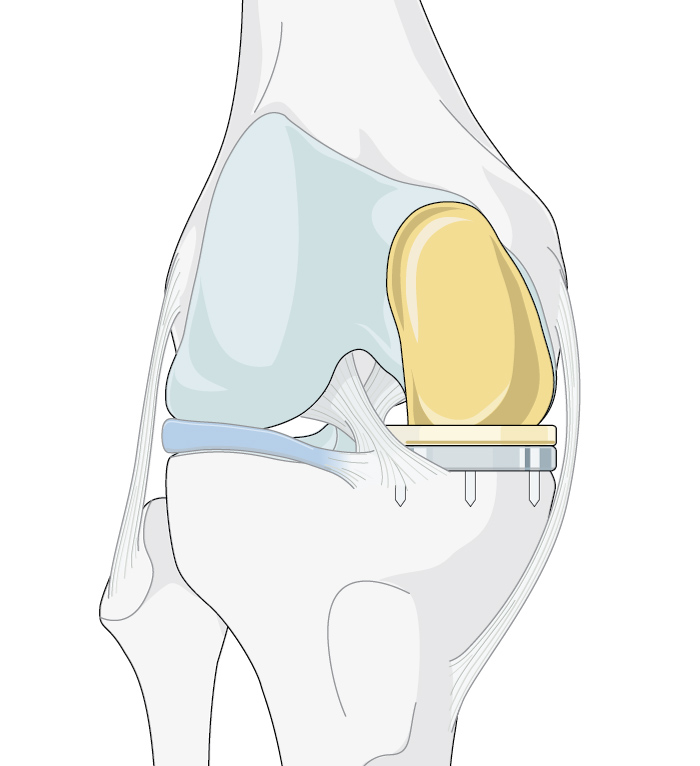

Figure 1. TKA, HTO, and UKA are all viable options to address osteoarthritis of the knee. However, there are situations that indicate the selection of one over the others.